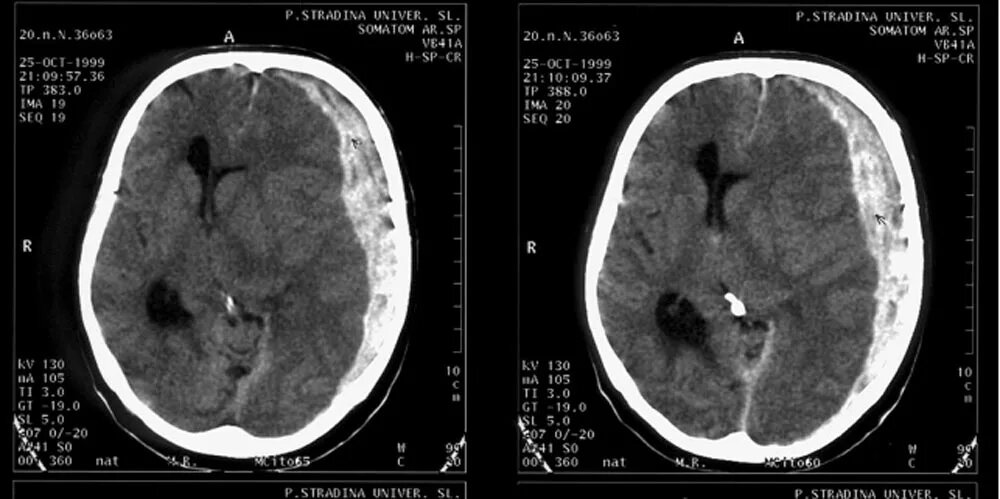

Тут в бокс постучала рентген-лаборант и сообщила, что пациентка уже на месте и можно начинать КТ. Я попросил маму никуда не уходить, поскольку скоро мы получим очень важную для всех нас информацию и мы с коллегой проследовали в кабинет компьютерной томографии. "Картинка" на мониторе томографа, конечно, всех удивила, но не ошеломила - вдавленный перелом левой теменной кости и довольно большая субдуральная гематома. Тут ещё из лаборатории токсикоцентра позвонили, что бензодиазепинов (аналогов хлозепида) в присланных на анализ промывных водах желудка не обнаружено, но зато они определяются в крови и моче пациентки, что можно объяснить использованием бригадой "скорой" реланиума для купирования судорог. Короче, "паззл" с анизокорией, прогрессирующим угнетением сознания и умеренной анемией сложился полностью. Юра дал нам и себе час времени на предоперационную подготовку...

Вот так выглядит на КТ огромная субдуральная гематома слева... Яндекс-фото